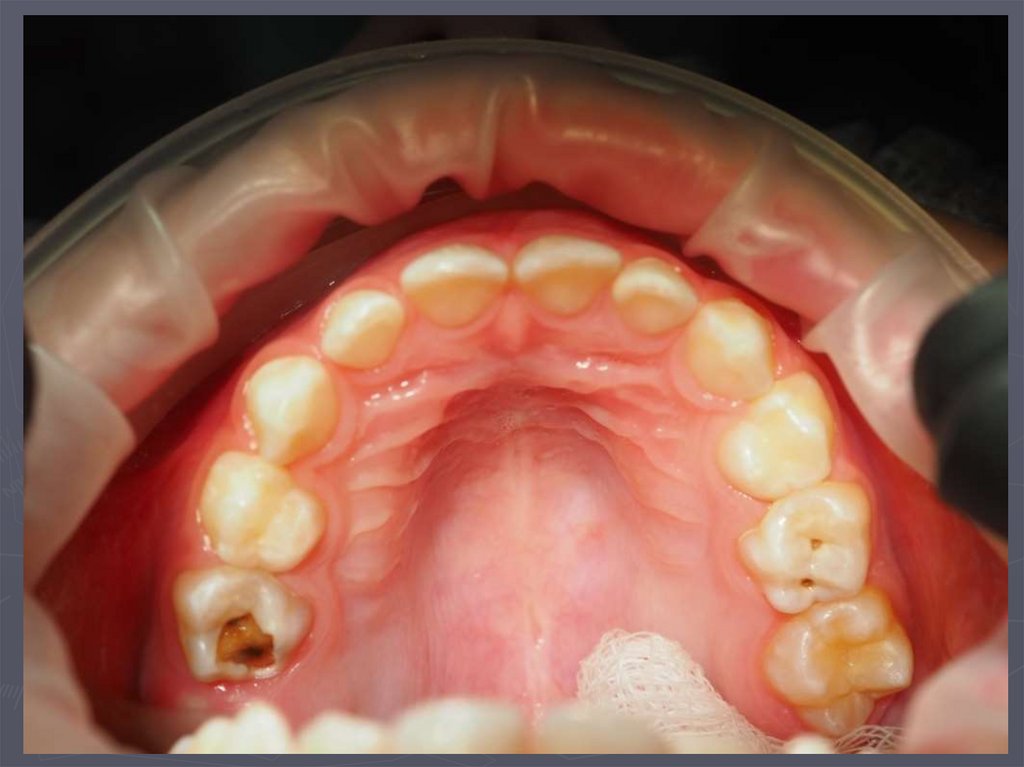

При клиническом осмотре выявляются:

► кариозные полости по глубине мелкие;

► имеют плоскую форму;

► входное отверстие в кариозную полость широкое

► эмаль по краям кариозной полости хрупкая;

► инфицированный дентин в полости влажный.

,

8. Циркулярный кариес

9. В возрасте после 4 лет КАРИЕС преимущественно развивается:

► у детей, которые плохо жуют;

► избегающих принимать жесткую пищу;

► у детей со сниженной самоочищаемостью полости рта;

► при неудовлетворительном гигиеническом состоянии

полости рта;

► у этих детей чаще поражаются моляры;

► локализуются кариозные полости на апроксимальных

поверхностях;

► полости имеют небольшое входное отверстие;

► эмаль по краям кариозной полости нависает;

► эмаль хрупкая, тонкая;

► дентин разной плотности.